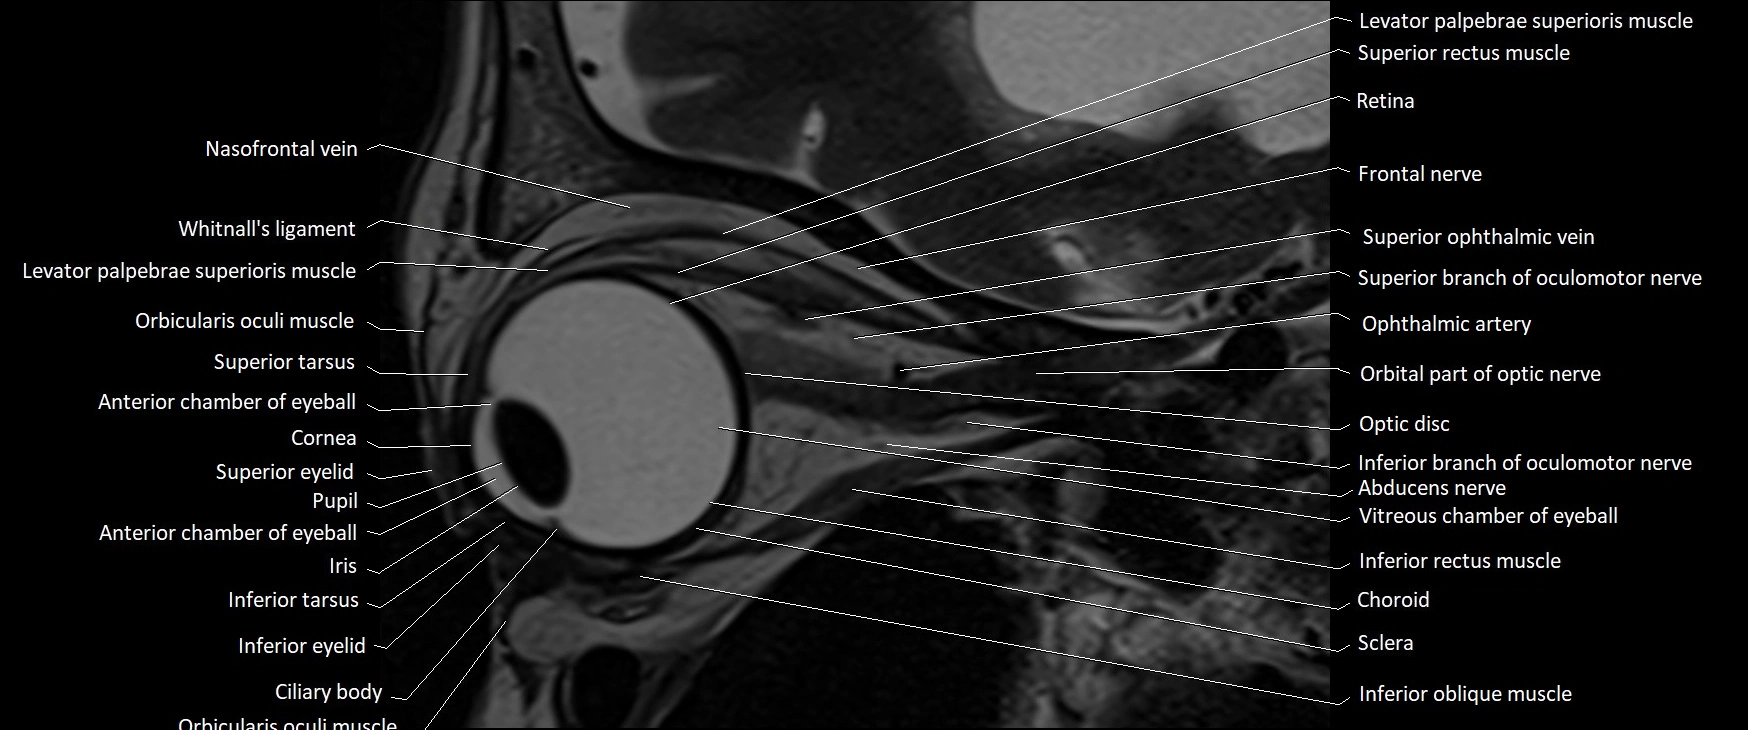

- Abducens nerve (Cranial nerve VI)

- Abducens nerve (orbital part )

MRI images